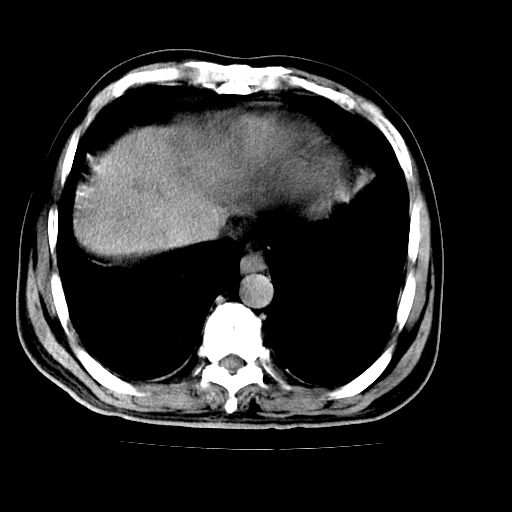

男,66岁,上腹部不适、黄染一周。彩超示:肝左叶占位,肝内胆管扩张,胆总管扩张,胆总管占位?

胆囊缩小,其内胆汁浓缩,也提示梗阻部位应该位于胆囊管起始部以上或是胆囊管受累及,支持肝外胆管癌。

肝左叶不规则软组织肿块影,边缘不规整邻近肝实质受累分界不清;肝内胆管(左叶)明显扩张成“软藤状”,诊断:肝左叶胆管细胞癌。